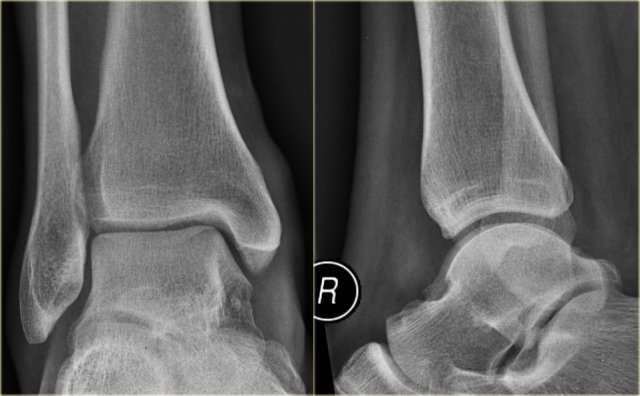

The images show an obvious Weber B fracture.

On the AP-view the linear lucency is the clue to a tertius fracture (red arrow).

It results from subtle malalignment of the fracture fragment.

Likewise in some cases malalignment can result in a linear density.

Trimalleolar Weber B fracture Trimalleolar Weber B fracture

In this case there is a Weber B fracture with avulsion of the medial malleolus.

The bright line on the AP-view indicates a large tertius fracture fragment.

This tertius fracture can also be seen on the lateral view, but in many cases we need all the information of both the lateral and AP-view to diagnose a tertius fracture.